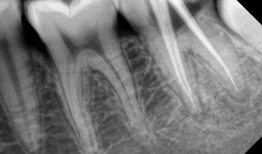

根管治疗视频,从视频学习根管治疗技巧与流程

最近是不是牙齿疼得你坐立不安,连笑容都变得苦涩了呢?别担心,今天就来给你揭秘一下那个听起来有点吓人的根管治疗,让你对这个过程有个...